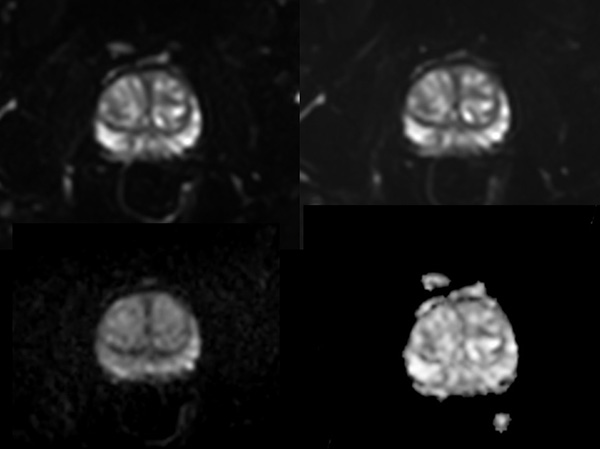

A 60-year-old male with elevated PSA and weak urinary stream underwent MRI. The exam includes high resolution DWI and ADC mapping as well as dynamic imaging. The prostate gland measures 5.2 x 4.4 x 5.9 cm in maximal transverse, AP, and craniocaudal dimensions, respectively, corresponding to an approximate glandular volume of 70 ml. Heterogeneous nodular hypertrophy is seen along the central transitional zone, with hypointense pseudo capsule, indicative of BPH, without dominant T2-hypointense nodules. Patchy T2-hypointense foci are noted throughout the peripheral zone bilaterally at the base, mid-gland and apex, with total PI-RADS score 6, so probably benign. No dominant nodular areas of restricted diffusion are evident. A geographic T2-hyperintense focus in the peripheral zone at the right base to mid-gland, paramidline shows asymmetric restricted diffusion, total PI-RADS score 10. No dominant lesions, greater than 1 cm. Clinical correlation and follow-up are advised.